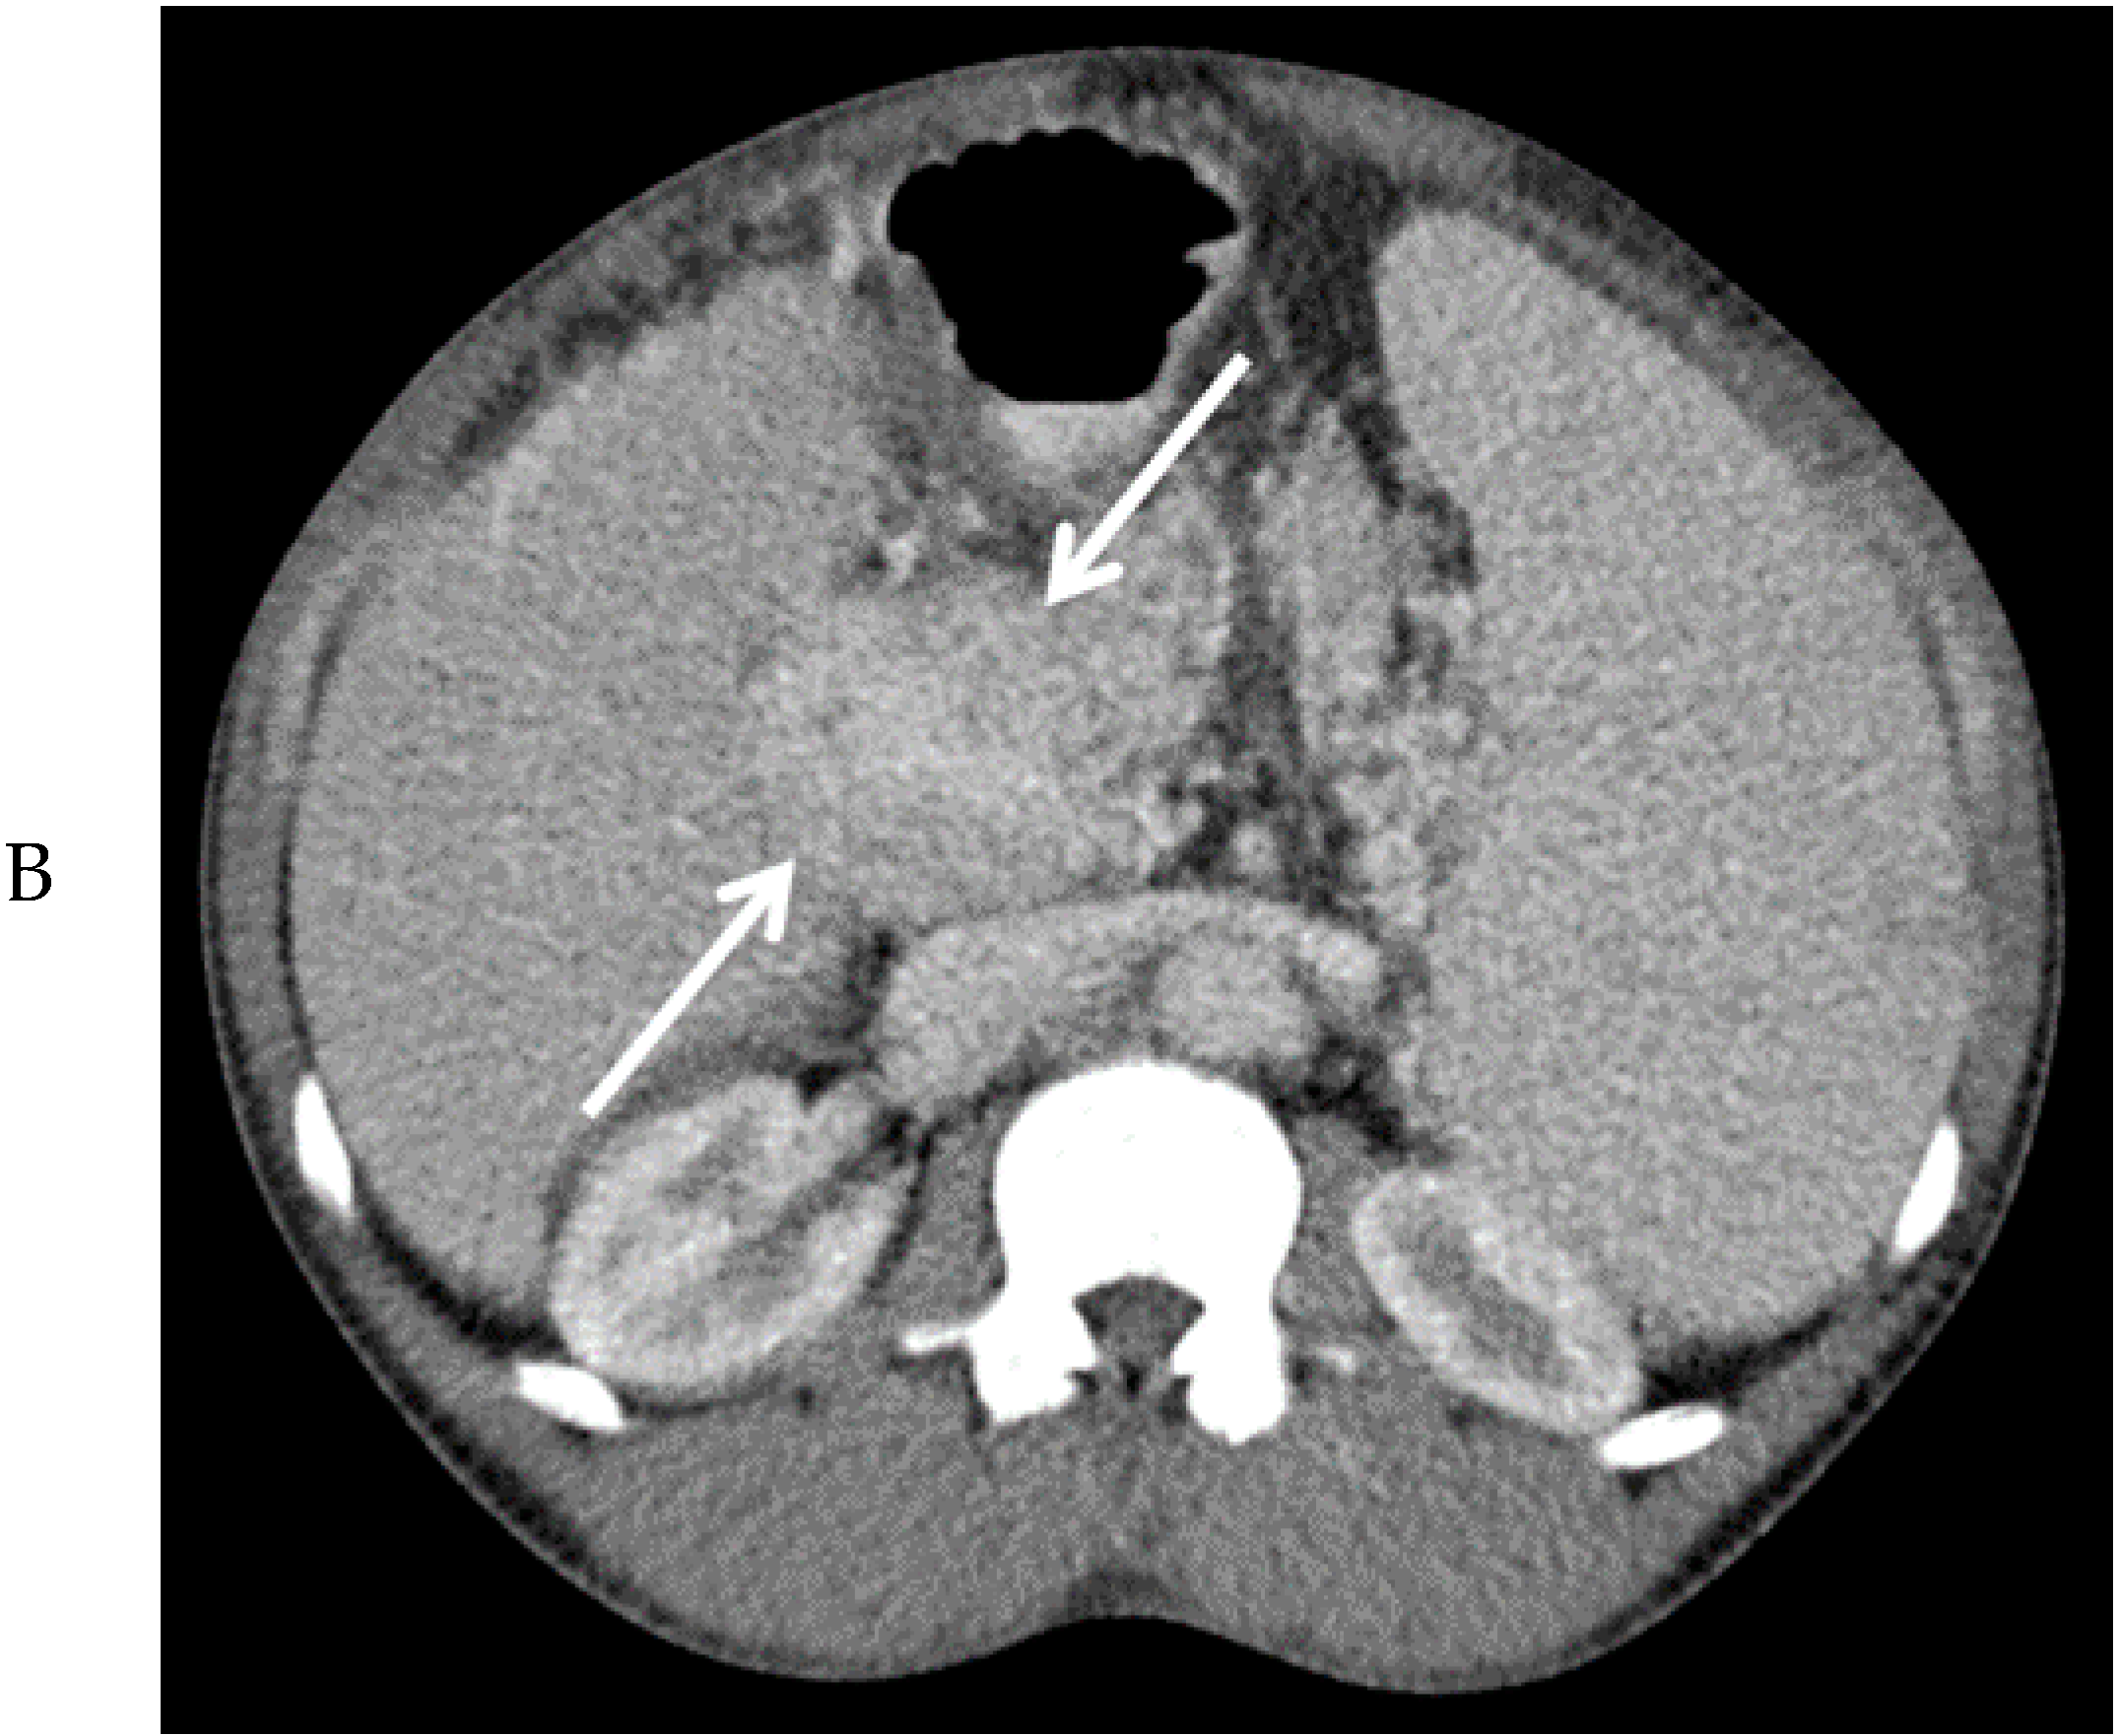

Figure 2.

Computed tomography images of the mass in the upper abdomen (arrows) in the arterial (A) and portal venous phase (B).